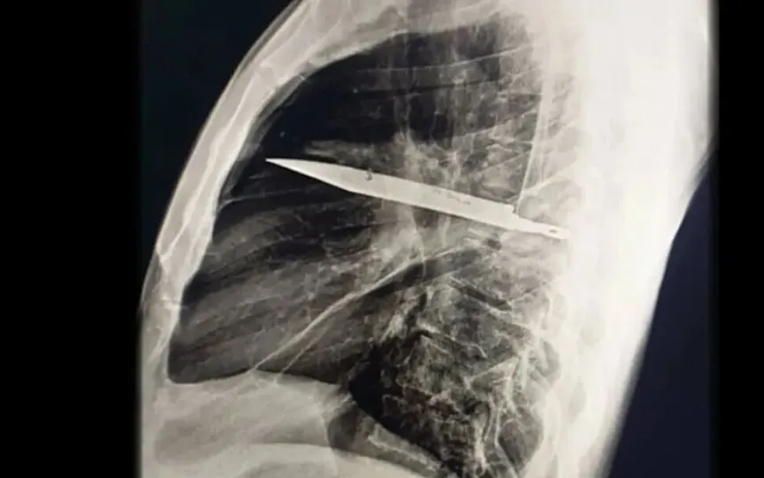

Khi thăm khám, bác sĩ nhận thấy ngực phải của bệnh nhân không nở ra đầy đủ khi hít vào, kèm theo lỗ rò rỉ dịch mủ có mùi hôi. Kết quả chụp X-quang khiến toàn bộ ê-kíp choáng váng: một lưỡi dao lớn gãy nằm gọn trong khoang ngực, kéo dài từ vùng xương bả vai phải đến trước xương sườn.

Phim chụp X-quang ngực của bệnh nhân cho thấy một lưỡi dao lớn găm vào giữa lồng ngực